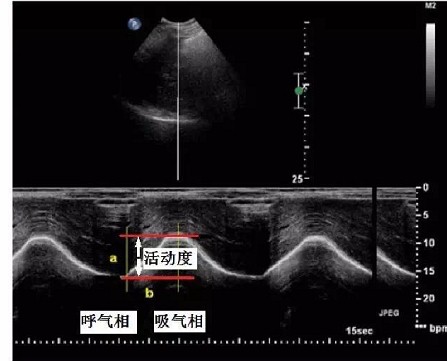

膈肌活动(DE)超声评估:包括膈肌厚度和膈肌移动度,能较直观的观察膈肌活动时的的空间动量。

平静呼吸膈肌活动度cm

<1

>2